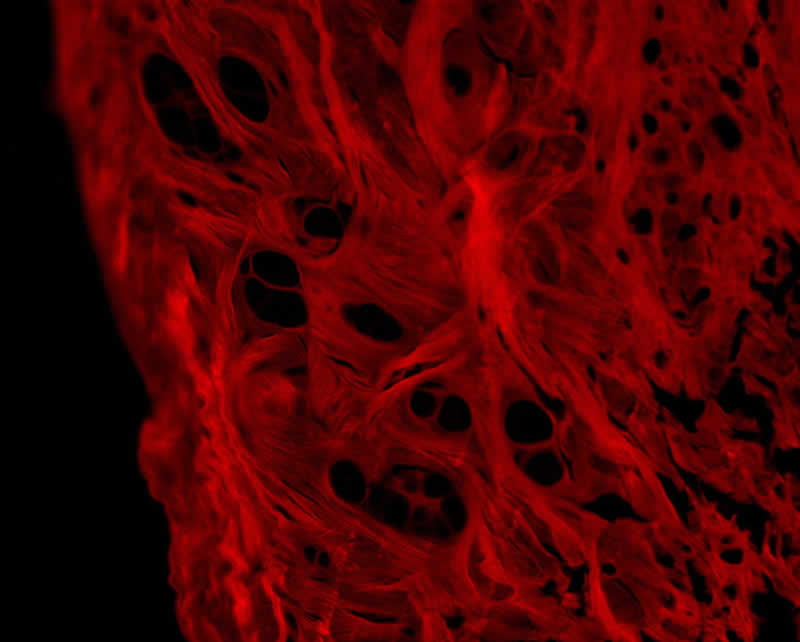

Kollagen ist das am häufigsten vorkommende Protein im menschlichen Körper. Es sorgt für Festigkeit und Elastizität in Haut, Knochen, Sehnen, Bändern und Knorpeln. Besonders für Sportler spielt die Stabilität dieser Strukturen eine zentrale Rolle. Wer regelmäßig trainiert, setzt seine Gelenke, Sehnen und Bänder einer hohen Belastung aus. Ein Mangel an Kollagen kann dazu führen, dass diese Strukturen an Festigkeit verlieren, was das Risiko für Verletzungen erhöht.

Strukturprotein Kollagen im Sport und die WirkungBildquelle: Unsplash.com / Tayfun Dikmen